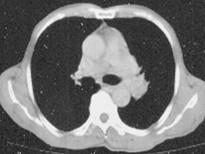

问题 60岁,男,有长期抽烟史,左声带麻痹、声音嘶哑2个月,请结合胸片和CT图,选出最可能的诊断 ( )

选项 A.肺癌 B.肺结核 C.尘肺 D.肺炎 E.肺结节病

答案 A